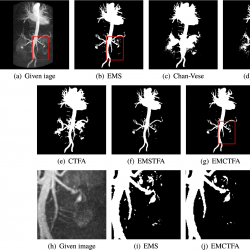

Example 4.

This example is one slide of 3D CE-MRA image of the abdominal vascular system whose size is $512\times 512$ (Fig. 7(a)) from http://www.mr-tip.com. Figures 7(b)–(g) show the results of vessel extraction by EMS, STFA, Chan-Vese, CTFA and the presented methods, respectively. In our method, we used $\alpha =1$ and $\beta =0.15$ to segment this MRA image.

Obviously, the segmented vessels by Chan-Vese give unsatisfactory results. Although STFA and CTFA algorithms detect some thinner vessels, it is unable to separate regions of the background whose intensity is close to the vessel intensity. For this reason those methods have unsatisfactory results in this case. To compare EMS algorithm and the presented method closely, we enlarge the rectangular boxes in Figs. 7(e)–(g). They exhibit that EMS algorithm has many artifacts which are well reduced by our method. Table 1 shows that EMCTFA method converges in 6 iterations. Also, it shows that the presented method converges faster than CTFA method. In the presented method, at the first iteration, the number of pixels that are not classified is 4146 pixels, while in the CTFA method it is 30871 pixels.

infor435_g007.jpg

Fig. 7

Example 4. CE-MRA image of abdominal vascular system extraction. (a) Given image; (b)–(e) Results by EMS, STFA, Chan-Vese, CTFA and EMSTFA methods, respectively; (g) Results of our EMCTFA method; (h)–(j) are the zoomed-in red rectangular parts of (a), (b) and (g).